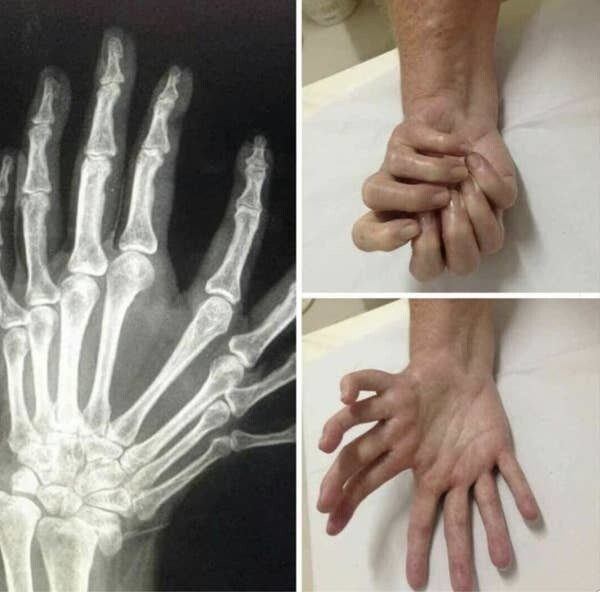

Существует также синдром зеркальной руки, когда у человека две кисти (без больших пальцев) вместо одной. Научное название этой врожденной аномалии — ульнарная димелия

А еще существует отклонение, при котором у большого пальца три фаланги вместо двух, из-за чего он становится намного длиннее обычного